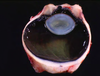

Cataract

The most common disease of the lens

Swelling/degeneration of lenticular fibersopacity

Lens response to injury:

Hydropic swelling of injured fibersfiber fragmentation & disintegration

Hyperplasia and fibrous metaplasia of lens epithelium

Posterior lens epithelial migration

When chronic (“hypermature”): shrinking and wrinkling of lens capsule and mineralization

What causes a cataract?

Radiation

Increased IOP (Glaucoma)

Endophthalmitis

Hereditary defect in lenticular metabolism

Diabetes mellitus (high glucose in aqueous)

Trauma

ANYTHING THAT DAMAGES THE LENTICULAR FIBERS!